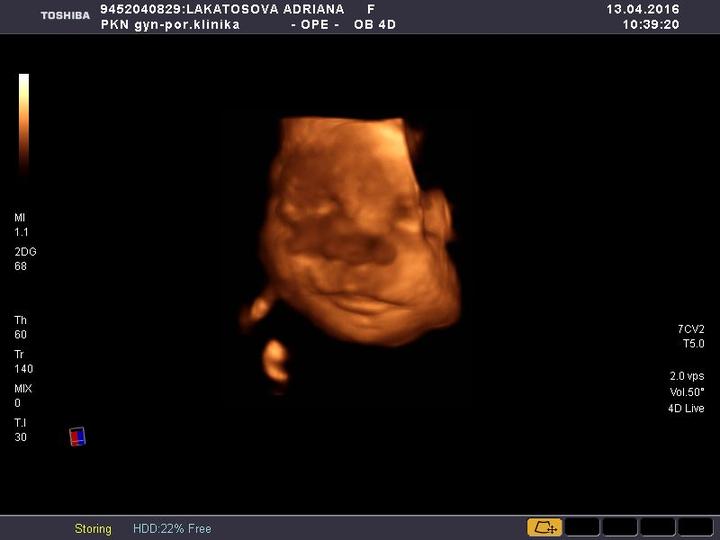

Tak holky dnes jsme byli na poslednim screeningu a mala ma 1700 gramu a 45 cm odhadem jinak uz zname presny termin porodu podle ultrazvuku 22. 6 a podle menstruace 26. 5 nevim co je presnejsi kdyztak mi prosim poradte podle ceho je to presne jinak laska nase je naprosto zdrava

tak zítra nás čeká 3D ultrazvuk 🙂